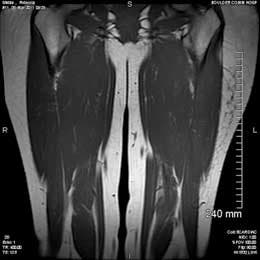

Becca Stubbs Severed Sacrum (Courtesy Photo)